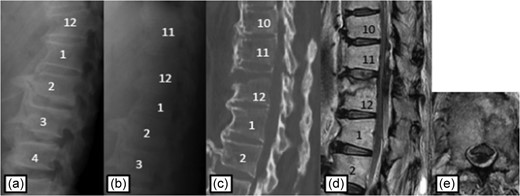

Plain radiographs on initial assessment (a) and on admission (b); Sagittal CT image (c) showing the hyperextension fracture at L1 and dislocation of it; MRI T2-weighted image (d, e) showing the severely compressed spinal cord at L1 level.